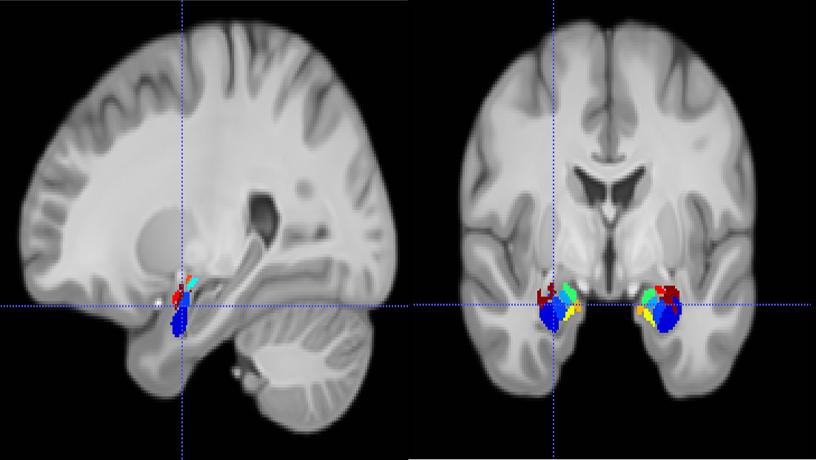

Magnetic resonance imaging depicting the location of a recording electrode in a subregion of the amygdala (colored regions). Credit: Salman Qasim/Columbia Engineering.